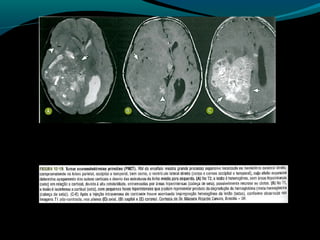

Astrocitoma anaplásico

Tumor com anaplasia focal ou difusa de origem

astrocítica classificado como grau III pela OMS;

33% dos astrocitomas;

Clínica variada;

Pacientes acompanhados com grau II que apresentam

deterioração clínica  III

Imagem:

Lesão infiltrativa com limites indefinidos;

É esperado infiltração do tumor na substância branca

adjacente;

Heterogeneidade de sinal é maior que no grau II, mas

predomina hipo em T1 e Hiper em T2 e FLAIR;

Imagem:

Após Gd: regiões de quebra da BHE;